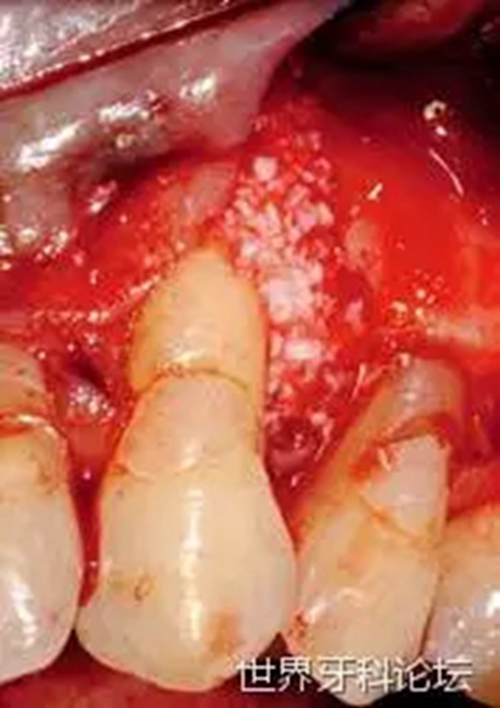

一位52歲女性患者,患局限型重度牙周炎。急性炎癥穩(wěn)定后,對(duì)患者進(jìn)行檢查,#23遠(yuǎn)中發(fā)現(xiàn)明顯的深骨內(nèi)袋(圖1)。瓣的設(shè)計(jì)同時(shí)考慮到解決目前的牙齦退縮(圖2)。仔細(xì)清創(chuàng),去除肉芽組織(圖3),之后,植入無機(jī)小牛來源羥基磷灰石(圖4)。

圖1:#23骨內(nèi)袋。

圖3:去除肉芽組織。

圖4:植骨。